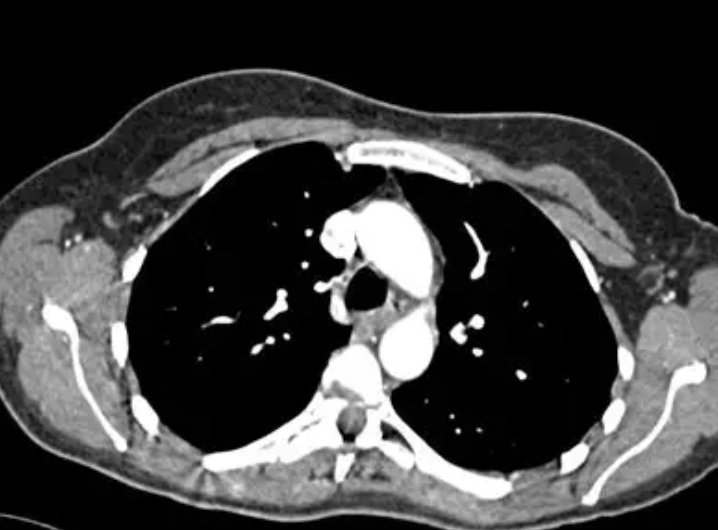

- 医疗影像 :必须保留病灶纹理、灰度层次,追求诊断可靠性。